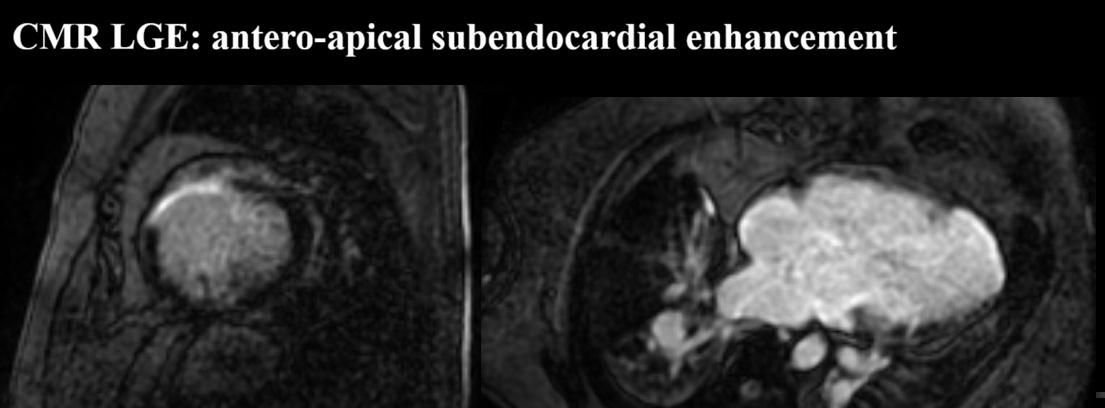

We report a 61-year-old man with unrepaired single-ventricle physiology (double inlet left ventricle, mesocardia, malposed great vessels) and stable chronic cyanosis (baseline SpO2 80–85%). In the absence of a “protective” pulmonary stenosis, lifelong high pulmonary flow and pressure led to pulmonary vascular remodeling and increased resistance, resulting in severe pulmonary arterial hypertension (PAH) with Eisenmenger-type physiology; the single ventricular pump is highly preload-, cardiac rhythm-, and systemic pressure–dependent. The course is complicated by acquired ischemic heart disease: an anterior acute coronary syndrome in 2015 in the setting of anomalous coronaries and supply–demand mismatch. Cardiac MRI showed severe dominant-ventricle dilation, EF ~33%, and antero-apical subendocardial late gadolinium enhancement. Right-heart catheterization confirmed severe PAH with PAP 120/22 mmHg (mean 55), PAWP 9 mmHg and PVR 6.2 WU, supporting initiation of triple PAH therapy (macitentan, sildenafil, selexipag) with close monitoring of systemic pressure and volume status. Clinical decompensations were triggered by atrial fibrillation or atrial tachycardia with high ventricular response, managed with rhythm and/or rate control (amiodarone, digoxin, cautious beta-blocker titration) and tailored decongestion. Non-invasive ventilation with positive pressures (BiLevel) was set conservatively given the effects of intrathoracic pressure on venous return and pulmonary circulation. Long survivors with DILV in natural history are exceedingly rare and appear to cluster into two phenotypes: “balanced” circulations with restricted pulmonary flow, and exceptional cases without protection who develop pulmonary vasculopathy. This patient belongs to the latter and is notable for triple PAH therapy; depressed systolic function may have mitigated pulmonary flow overload, contributing to a fragile equilibrium. Arrhythmic/sudden-death risk stratification in a single ventricle with scar led to ICD counselling, which the patient refused. Unrepaired DILV reaching the sixth decade with severe PAH is exceptional; management should remain physiology-driven.